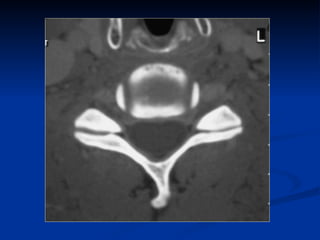

TDM cervicale  Acquisition hélicoïdale Matrice 512 x 512 Petite épaisseur de coupe Injection IV de PC: épidurographie Faible quantité de graisse dans le rachis cervical Reconstruction 2D/3D

TDM injectée Épidurographie Base de la sémiologie TDM des HD

TDM+INJECTION IV AVANTAGES Technique ambulatoire, généralisée Bonne visualisation des structures osseuses Bonne sensibilité Reconstruction 2D/3D LIMITES Artéfacts d’épaule Injection IV de PC jamais anodine Médiocre pour l’étude de la moelle Peu sensible en cas de dégénérescence débutante.

TDM injectée ÉpidurographieBase de la sémiologie TDM des HD

TDM+INJECTION IV AVANTAGESTechnique ambulatoire, généralisée Bonne visualisation des structures osseuses Bonne sensibilité Reconstruction 2D/3D LIMITES Artéfacts d’épaule Injection IV de PC jamais anodine Médiocre pour l’étude de la moelle Peu sensible en cas de dégénérescence débutante.